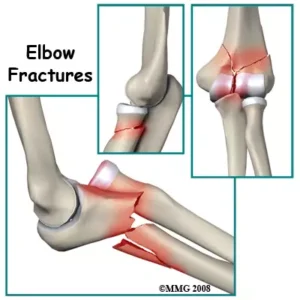

Elbow Fractures

Breaks caused by falls or accidents requiring precise treatment and rehabilitation.